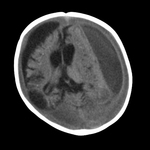

CT scan revealing subdural haemorrhage extending over the right convexity and in the intrahemispheric region, as well as enlargement of the extra-axial fluid spaces

From the personal collection of Alice Newton, MD; used with permission